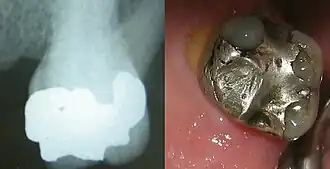

Amalgame dentaire

En dentisterie, un amalgame dentaire est un matériau utilisé pour obturer les cavités résultant de l'élimination de tissus dentaires affectés par des caries.

Bien qu'on l'appelle aussi « plombage », l'amalgame dentaire ne contient pas de plomb.

Il contient en revanche du mercure lié à d'autres métaux. Bien que la toxicité du mercure soit bien établie, la toxicité des amalgames reste controversée[1].